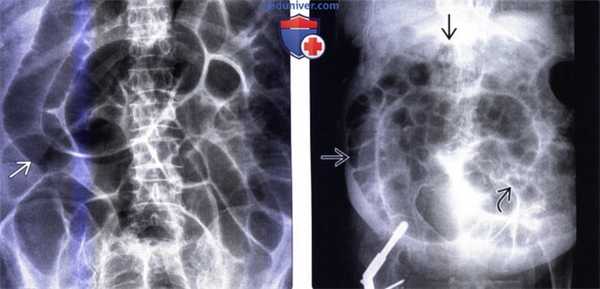

(Слева) На аксиальной КТ без контрастного усиления определяется непропорциональное расширение слепой и восходящей ободочной кишки по сравнению с нисходящей ободочной кишкой и тонкой кишкой, которые не выглядят патологически измененными. Также не определяется признаков обструкции ободочной кишки или заворота.

(Справа) На рентгенограмме в положении лежа на спине у пациента с илеусом толстой кишки после оперативного вмешательства определяется расширение всей толстой кишки и минимальное количество газа в тонкой кишке. Также визуализируются клипсы в коже в нижних отделах живота справа после трансплантации почки, выполненной ранее. (Слева) На рентгенограмме, выполненной в положении лежа на спине молодой женщине, которая недавно перенесла открытую операцию на сердце, и у которой возникло вздутие живота, определяется расширение мобильной слепой кишки до 10 см, и слегка менее выраженное расширение поперечной ободочной кишки. В желудок введен зонд для искусственного кормления.

(Справа) На повторной рентгенограмме, выполненной на следующий день этой же пациентке, определяется прогрессирующее расширение слепой кишки до 14 см, а также поперечной ободочной кишки. Было принято решение о декомпрессии путем внутривенного введения неостигмина, интубации ободочной кишки и аспирации ее содержимого.